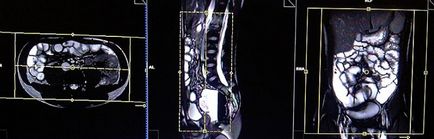

Tervezés tengelyirányú szeleteket a koszorúér síkban; blokk helye keresztirányban hasüregben, amint az ábrán látható. Ellenőrizze a helyét a blokk a 2 másik síkon. Ezek a szakaszok teljes mértékben meg kell terjednie a teljes hasüreget és a medence a gyomorból az a szint, a fancsonti. Annak megakadályozása érdekében műtermékek GDV kell használni fázist túlmintavételezésre (túlmintavételezés). Tájékoztassa a beteget, hogy lélegzet-visszatartás során képrögzítő csomagokat. (A mi osztály, azt utasítják a pácienseket be és ki kétszer, mielőtt „be és tartsa vissza a lélegzetét” elején a scan).

Mielőtt a következő lépést, intravénásán Buscopan 0,5-től 1 ml (per testtömeg) és 15-től 20 ml Gadolinium (súly szerint). várhatóan 1 perc (futás Buscopan akció néhány percet vesz igénybe), amíg a következő ciklusban.